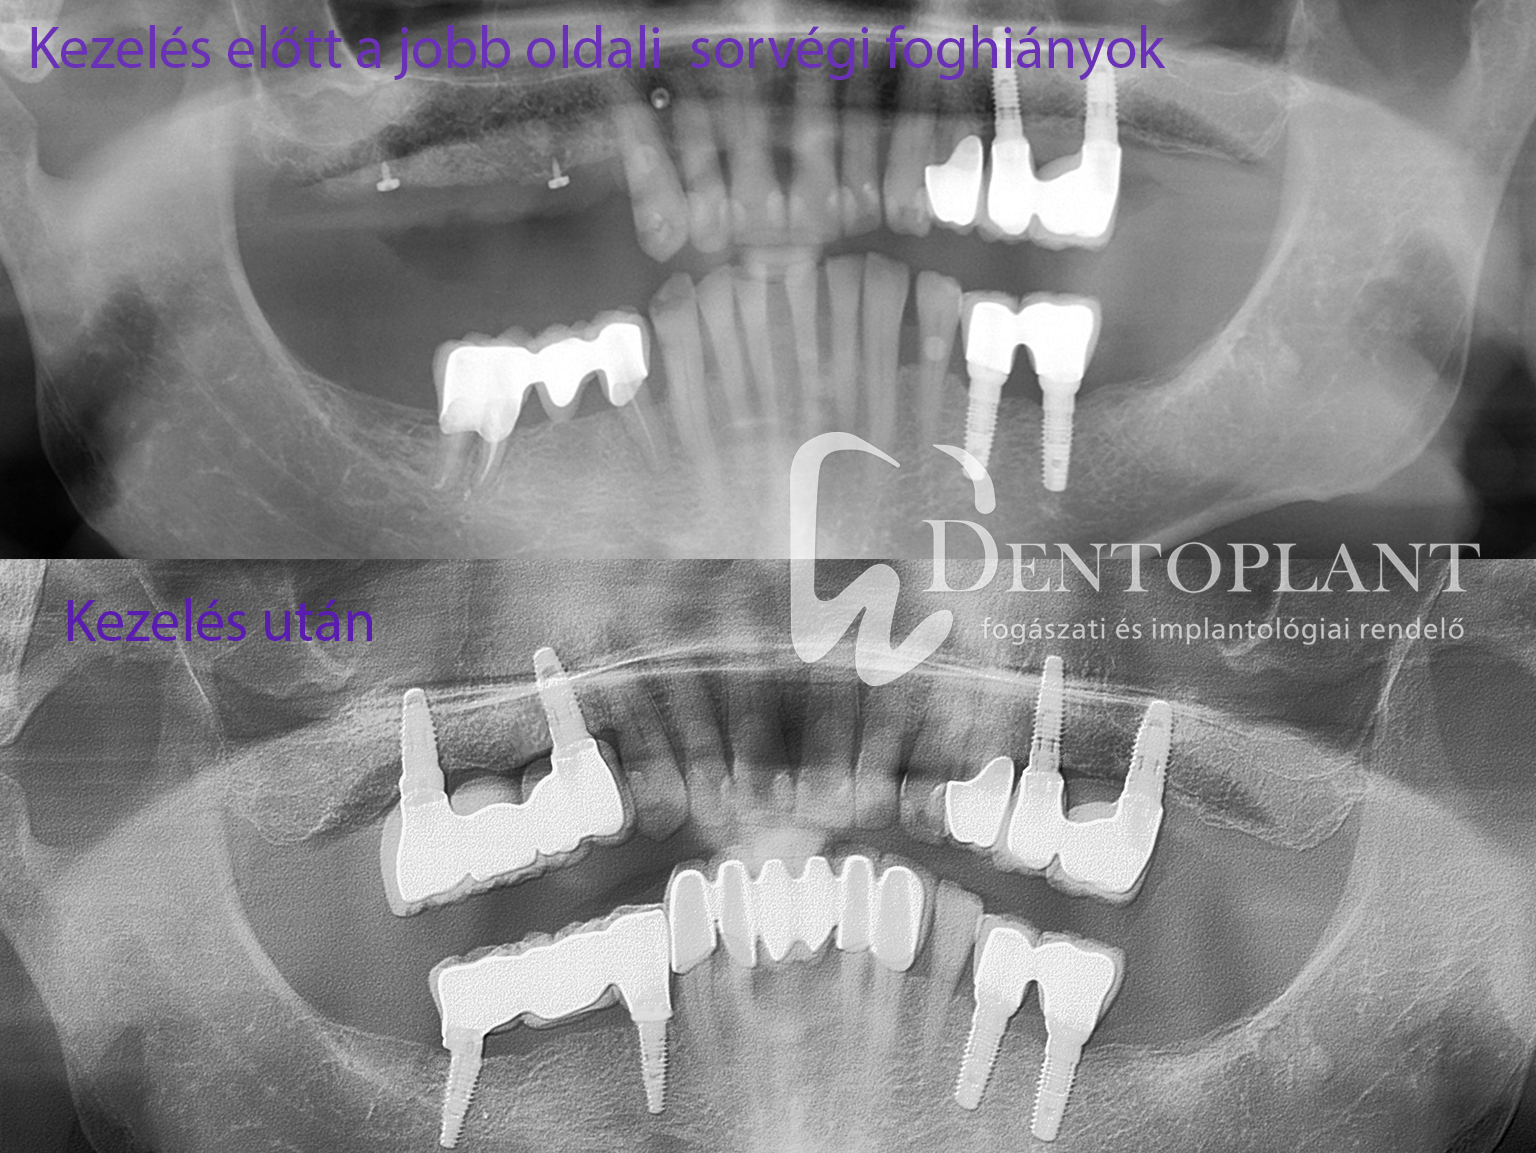

Amikor a sor végéről hiányoznak fogak, az fogpótlás szempontjából a páciensnek egy speciálisan nehéz helyzetet jelent, mert ilyen esetben fogpillér hiányában nincs lehetőség hagyományos fix hidat készíteni. Pedig a sorvégi foghiány megoldása kiemelten fontos, mert ilyenkor a rágófogak hiányával az étkezés és a rágás is nehézzé válik.  A sor végéről hiányzó fogak esetén rövidül a fogív, romlik a rágás hatékonysága és a szemben lévő fogakat sem tudjuk megfelelően használni, így idővel azok is elmozdulhatnak. A sorvégi foghiányok fogpótlásának megoldására a korszerű fogbeültetési módszerek a legmegfelelőbbek. Fogbeültetéssel megfelelő pilléreket kapunk, melyekre már a legmodernebb számítógéppel tervezett felcsavarozható rögzített hidakat készíthetjük el.

Fogbeültetéssel és számítógépes tervezéssel a legjobban használható rögzített hidakat tudjuk elkészíteni sorvégi foghiányok pótlására. Ez a páciensek számára olyan stabilitást és komfortot eredményez, hogy ugyanúgy tud majd rágni, mint korábban, sőt sokszor halljuk pácienseinktől, „hogy az implantátumon már jobban rág.”  Rendelőnkben évente nagy számú hasonló esetet kezelünk, az  1-2 foghiánytól a kétoldali sorvégi hosszabb hidakig. A műtét menete attól függ, hogy az állcsontban a foghiány helyén milyen a csont mennyisége és minősége. Amennyiben a beültetésre tervezett megfelelő helyen a csontállomány elegendő, akkor egy egyszerű fogbeültetést követő 3 hónapos gyógyulás után elkészülhet a híd. Ha viszont nincs megfelelő mennyiségű csont, akkor csontpótlással kell kiegészíteni a kezelést, ezáltal alakítva ki az implantátum számára megfelelő stabil alapzatot. A bemutatott sorvégi foghiányok megoldása során egyes pozíciókban nem volt elegendő a csontmennyiség a fogászati implantátum beültetéséhez, így a műtéti tervet csontpótlással kellett kiegészíteni.